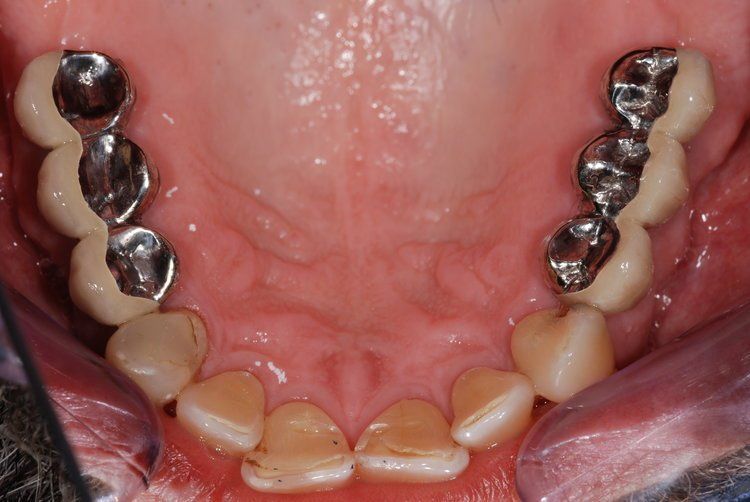

Unfortunately, it can be the case that a tooth (or teeth) are so badly damaged by trauma, bacteria, or tooth decay that removal is the only option. In this case, we recommend that a patient has dental implants inserted to replace any missing teeth. Modern dental implants are long lasting, strong, and look, feel, and function just like real teeth.

At the Dental Innovations clinic in Wasilla, AK, we specialize in single and multiple implant restorations. Our team can use a wide range of implant systems to provide patients with a full mouth of even, strong teeth. Contact our dental clinic today to arrange a consultation to discuss what dental implants may be the best for you.